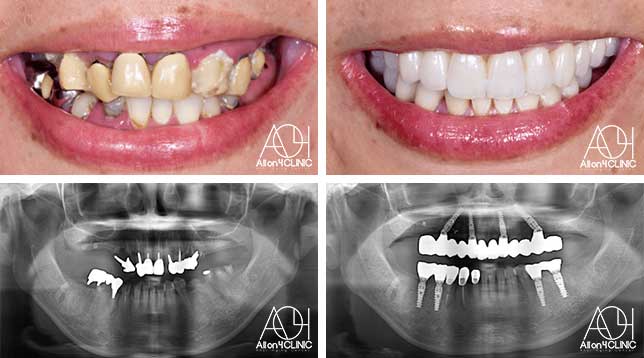

男性 / 65歳

日本各地のクリニックを受診し、カウンセリングを何回も受けているがどのクリニックで治療を受けるべきか迷っている。

治療詳細:ガイデッドサージェリーにてインプラント埋入。骨量が少量であったためザイゴマインプラントにて治療。

費用:¥5,720,000(税込)『モニター割引適用』『オリジナル動画撮影協力あり』

リスク:治療後の口腔管理が不適切な場合、埋入したインプラント周囲に感染・炎症を起こし、脱落する可能性がございます。